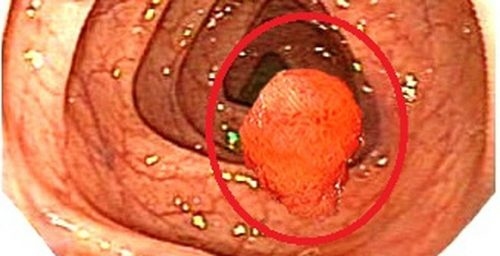

Polyp trực tràng không chỉ đem đến nhiều phiến toái, làm giảm chất lượng cuộc sống mà còn có thể biến chứng thành ung thư đe dọa đến tính mạng của người bệnh. Cắt polyp trực tràng là cách điều trị giúp loại bỏ hoàn toàn polyp, ngăn ngừa các biến chứng nguy hiểm của bệnh.

Việc cắt polyp trực tràng thường được tiến hành trong quá trình nội soi. Khối polyp sau khi cắt bỏ sẽ được gửi đến phòng xét nghiệm để xác định tính chất lành tính hay ác tính. Nếu kết quả xét nghiệm lành tính, việc điều trị polyp trực tràng được xem là hoàn tất, người bệnh được xuất viện và theo dõi tình trạng sức khỏe tại nhà. Nếu kết quả xét nghiệm ác tính, sẹo cắt polyp còn tế bào ung thư, người bệnh sẽ phải tiến hành phẫu thuật cắt bỏ phần trực tràng chứa tế bào ung thư và được theo dõi điều trị tại bệnh viện.